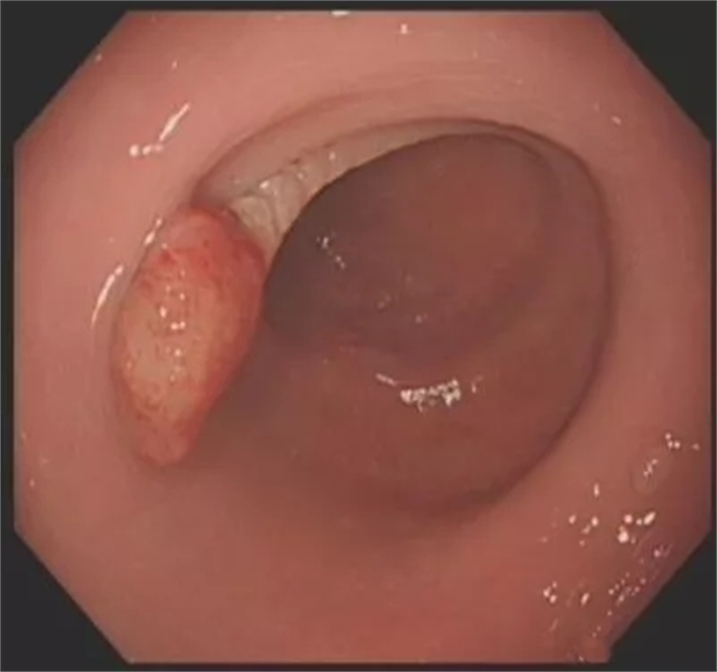

患者女性,42岁,无明显不适症状,例行肠镜检查,乙状结肠处发现一枚大小约1.0cm×1.5cm山田Ⅳ型息肉。